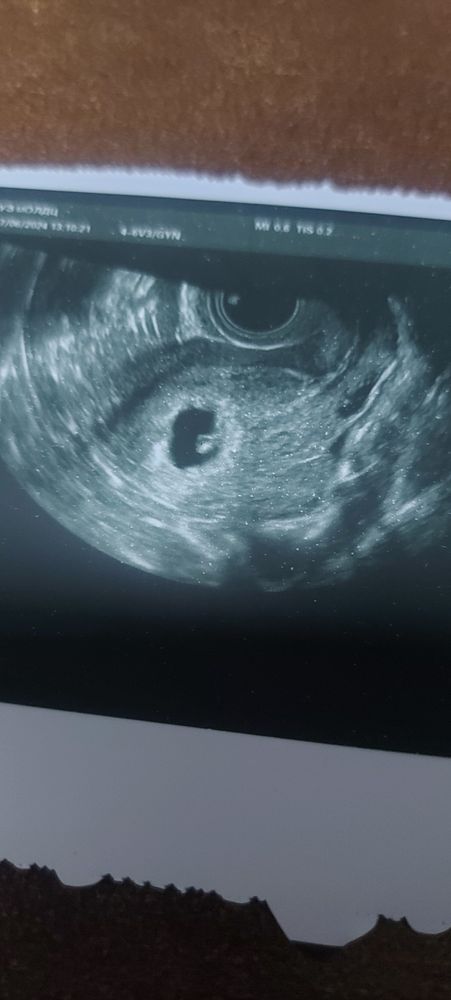

Наше первое УЗИ❤️❤️❤️

Алина А, незнаю почему 8 недель указывает здесь, вообще акушерских 7 недель , по УЗИ 6 недель поставили

Марина, поняла теперь. Т е. 7 полных и идет восьмая